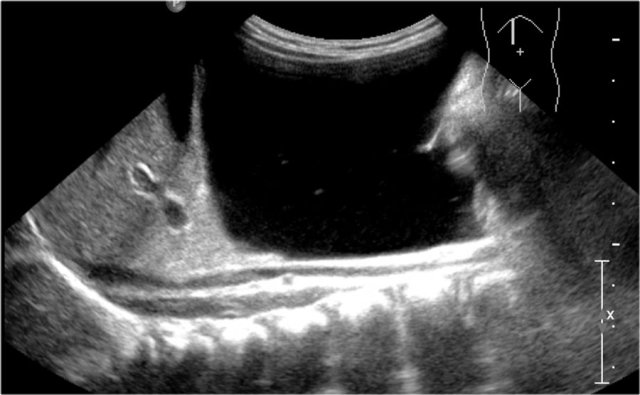

One-year-old boy was referred with a diagnosis of a cystic nephroblastoma.

Ultrasound detected a huge cyst in the middle of the abdomen.

When examined from the left flank with a high frequency linear array probe some parenchymal tissue was visible surrounding very dilated calyces. This is compatible with an extreme hydronephrosis.

At first it was thought that there were some solid parts in the cyst.

But when pressure was applied with the probe this proved to be debris.

MRI depicts the hydronephrosis with more overview.

The cause was a pyeloureteric stenosis.

The left kidney had 33% split renal function on renography.

A pyelum reconstruction was successfully performed.